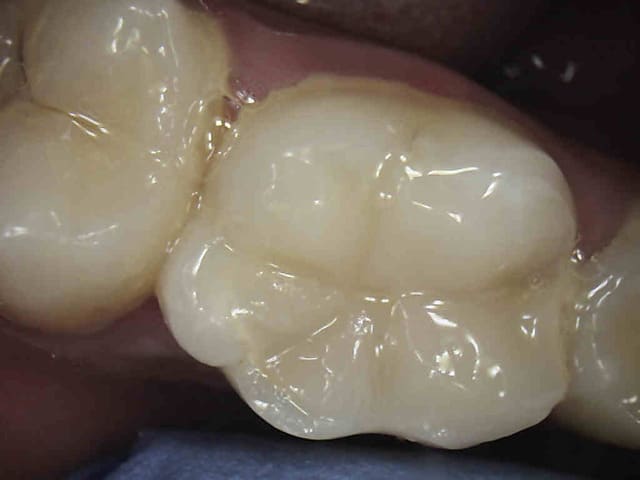

C'est quoi la proba d'avoir une deuxième bio à 5 canaux en 2 semaines?

(la radio excentrée est dégueulasse, mais ça montre les doubles courbures, quelques peu minimisées par l'angulateur...